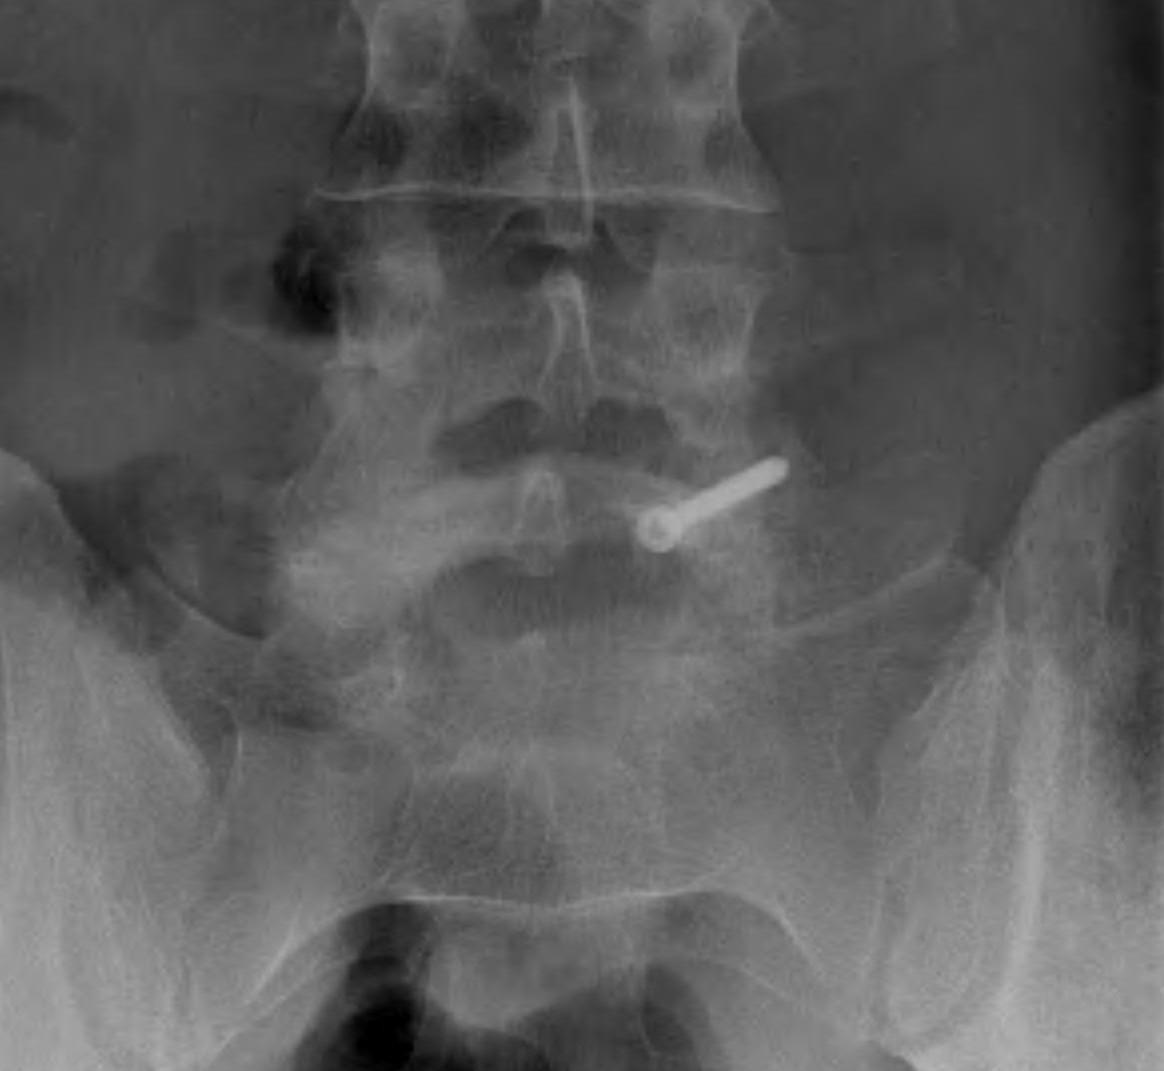

Fusion of Pars

Indication

- normal discs and facets

- pain relieved by pars injection

- failure brace / non operative treatment

- minimal slip

Technique

- lesion identified / debrided / iliac crest bone graft

Options ORIF

1. Screw across lytic defect

- unilateral defect

2. Pedicle screw + laminar hook

- bilateral defect

3. TBW spinous process and transverse process

Results

Kakluchi et al JBJS Am 1997

- 16 patients with failure non operative treatment bilateral pars defect

- pain relieved by pars injection with LA

- pedicle screw + lamina hook

- nerve root decompression where required

- union in all 16

- 3 patients only had occasional back pain